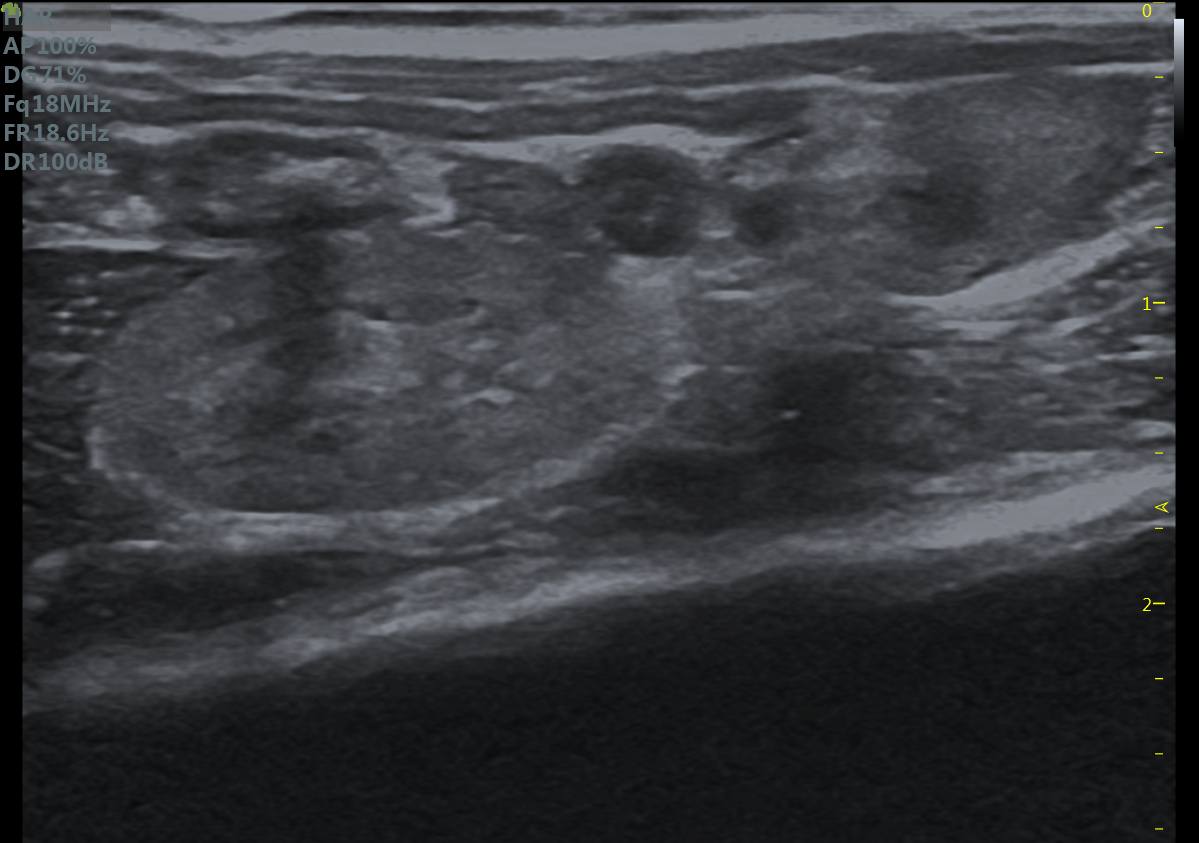

小鼠长轴M型 小鼠短轴M型

小鼠长轴B型 小鼠短轴B型

大鼠短轴M型 大鼠长轴M型

大鼠长轴B型 大鼠主动脉弓